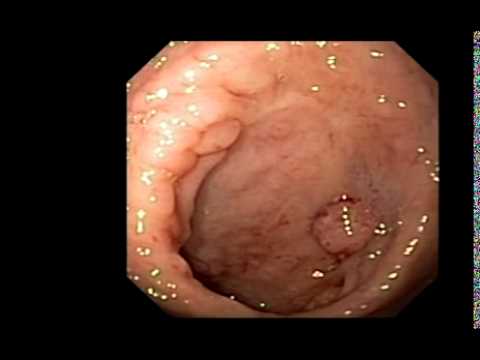

Côlon, Anatomie Post-Chirurgicale Anormale, Sténose...

Le film montre une image endoscopique du côlon avec une légère sténose de l'anastomose colorectale.